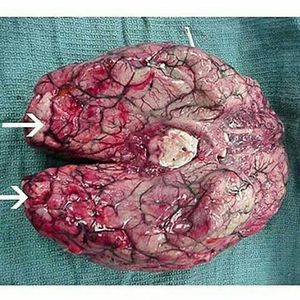

The arrows are pointing to some hemorrhage in the brain of a healthy young person who went swimming in warm, stagnant water. Some of the water got into their nose. Afterwards, they complained of a headache, then two days later fell into a coma and died. What could have caused this person's death? Answer: It's Nagleria fowleri, the BRAIN EATING AMOEBA! These critters live in warm stagnant water and enter the brain through the nasal passages, causing a deadly infection called primary amebic meningoencephalitis. Infections are rare and there are only 133 documented cases in the US. Most occur in the southern states during the summer months @medicalcortex #med #medical #hospital #surgery #medicine #medico #nurse #brain #pathology #hemorage #medstudent #futuredoctor #neurosurgery #neurology #autopsyofamerica #autopsy #medstudents #amoeba #f4f #l4l #premed #usmle #doctor #medicalstudent #emergency